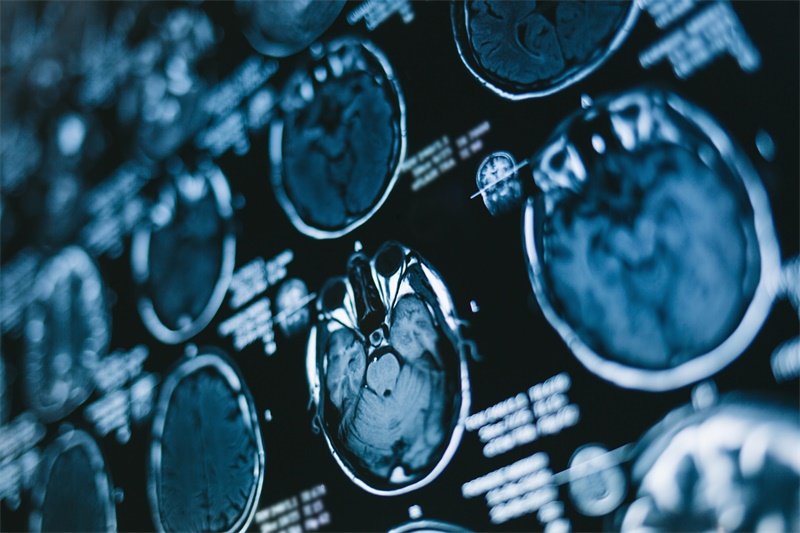

在诊断方面,头颅CT和MRI是常用的检查方法。CT检查可发现丘脑区有异常密度影,肿瘤边界可能不清;MRI则能更清晰地显示肿瘤的位置、大小、形态以及与周围组织的关系,还能判断肿瘤是否有出血、坏死等情况。此外,还需要结合患者的症状、体征以及其他辅助检查,如脑血管造影等,以明确诊断。

诊断丘脑炎症性病变需要结合临床表现、实验室检查和影像学检查。实验室检查包括血常规、脑脊液检查等,血常规可显示白细胞计数升高,以中性粒细胞为主;脑脊液检查可发现压力增高,细胞数增多,蛋白含量升高,糖和氯化物正常或降低。影像学检查中,MRI对早期病变的显示更为敏感,可发现丘脑区有异常信号影,呈长T1、长T2信号。

在诊断方面,头颅CT是鉴别丘脑梗死和出血的首选方法。丘脑梗死在CT上表现为低密度灶,边界相对清晰;丘脑出血则表现为高密度灶,边界清楚。MRI对早期梗死的显示更为敏感,可在发病后数小时内发现异常信号。

影像学检查

如前所述,头颅CT和MRI是边缘系统病变诊断中常用的影像学检查方法。CT检查具有快速、便捷的优点,能够快速发现脑出血、脑肿瘤等病变;MRI则对脑梗死、炎症性病变等的显示更为清晰,能够提供更详细的病变信息,如病变的位置、范围、性质等。此外,正电子发射断层扫描(PET)等检查也可用于评估边缘系统的代谢和功能状态,帮助诊断某些疑难病变。